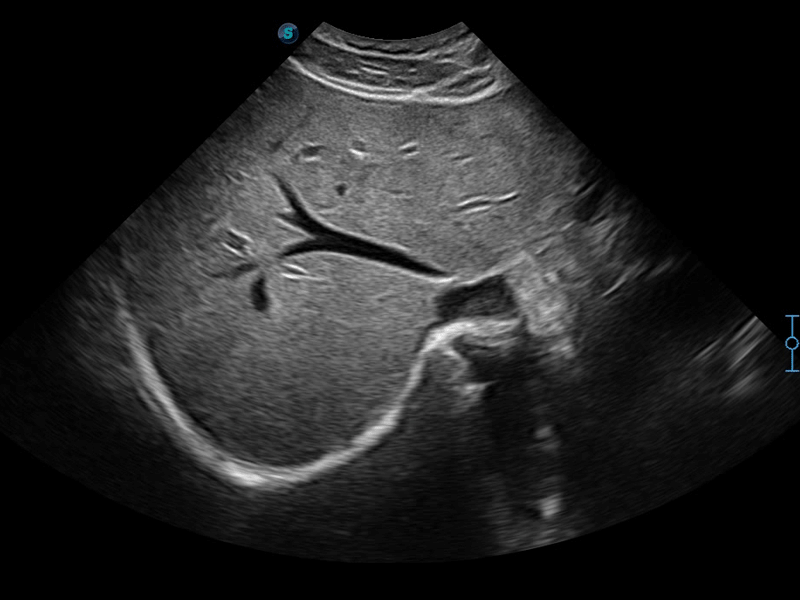

開立醫(yī)療通過不斷的技術(shù)創(chuàng)新,為大眾的生命健康提供持續(xù)關(guān)愛。P12 Plus采用全新一代超聲成像平臺(tái),新平臺(tái)旨在將真實(shí)還原組織解剖結(jié)構(gòu)作為首要目標(biāo)。平臺(tái)采用全新集成化硬件模塊,搭載新一代芯片,系統(tǒng)性能得到大幅提升,為您的診斷提供了豐富的臨床信息。優(yōu)異的圖像表現(xiàn),豐富的探頭配置,全面的應(yīng)用功能,為您日常診斷提供了可靠的助手。

P12 Plus

彩色多普勒超聲診斷系統(tǒng)